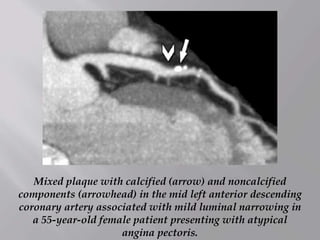

Mixed plaque with calcified (arrow) and noncalcified

components (arrowhead) in the mid left anterior descending

coronary artery associated with mild luminal narrowing in

a 55-year-old female patient presenting with atypical

angina pectoris.